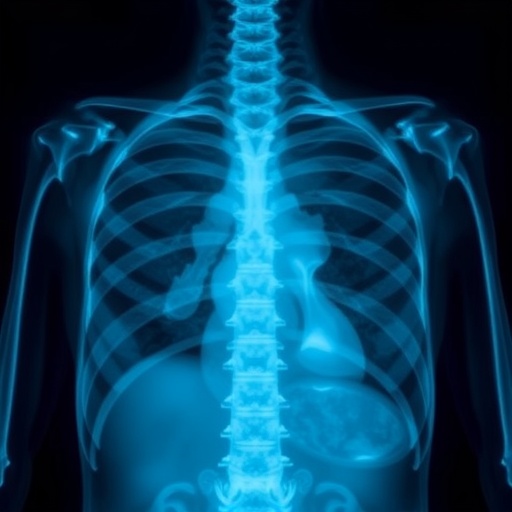

Utilizing chest X-rays presents a challenging task for AI models. These images often contain a plethora of anatomical variations, making it difficult for diagnostic systems to distinguish between normal placements and deviations of catheters and lines. The research team overcame these challenges by fine-tuning their model with various datasets that encapsulate a wide range of cases. This comprehensive dataset served as a bedrock for the knowledge distillation process, allowing the student model to learn from the nuanced differences in image presentations.

In the rapidly evolving field of medical imaging, advancements in artificial intelligence (AI) are paving the way for more accurate and efficient diagnostics. A recent study conducted by Tran-Anh et al. sets a new precedent with its innovative approach to detecting malpositioned catheters and lines in chest X-rays. This research brings the concept of knowledge distillation to the forefront, allowing for improved performance in a complex clinical environment. Traditional methods of identifying misaligned medical devices can be time-consuming and prone to errors. However, this study introduces a multiple teacher-student model that enhances the reliability of detecting such critical errors.